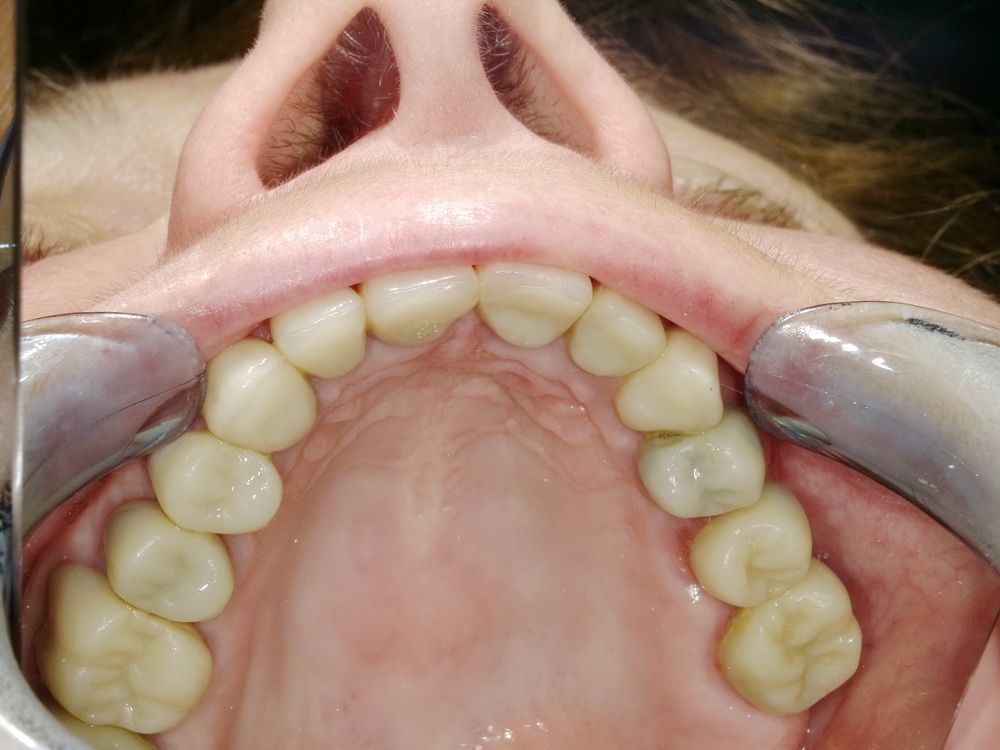

Nach mehreren Monaten Erprobungszeit der funktionstherapeutisch eingestellten Bisslage beginn nunmehr die Umsetzung der Versorgung mit Laborgfertigten Dauerprovisorien in eine Versorgung mit definitiven zahntechnischen Kronen.

Die neue Versorgung beginnt mit der Entfernung der Dauerprovisorien im Unterkieferseitenzahnbereich.